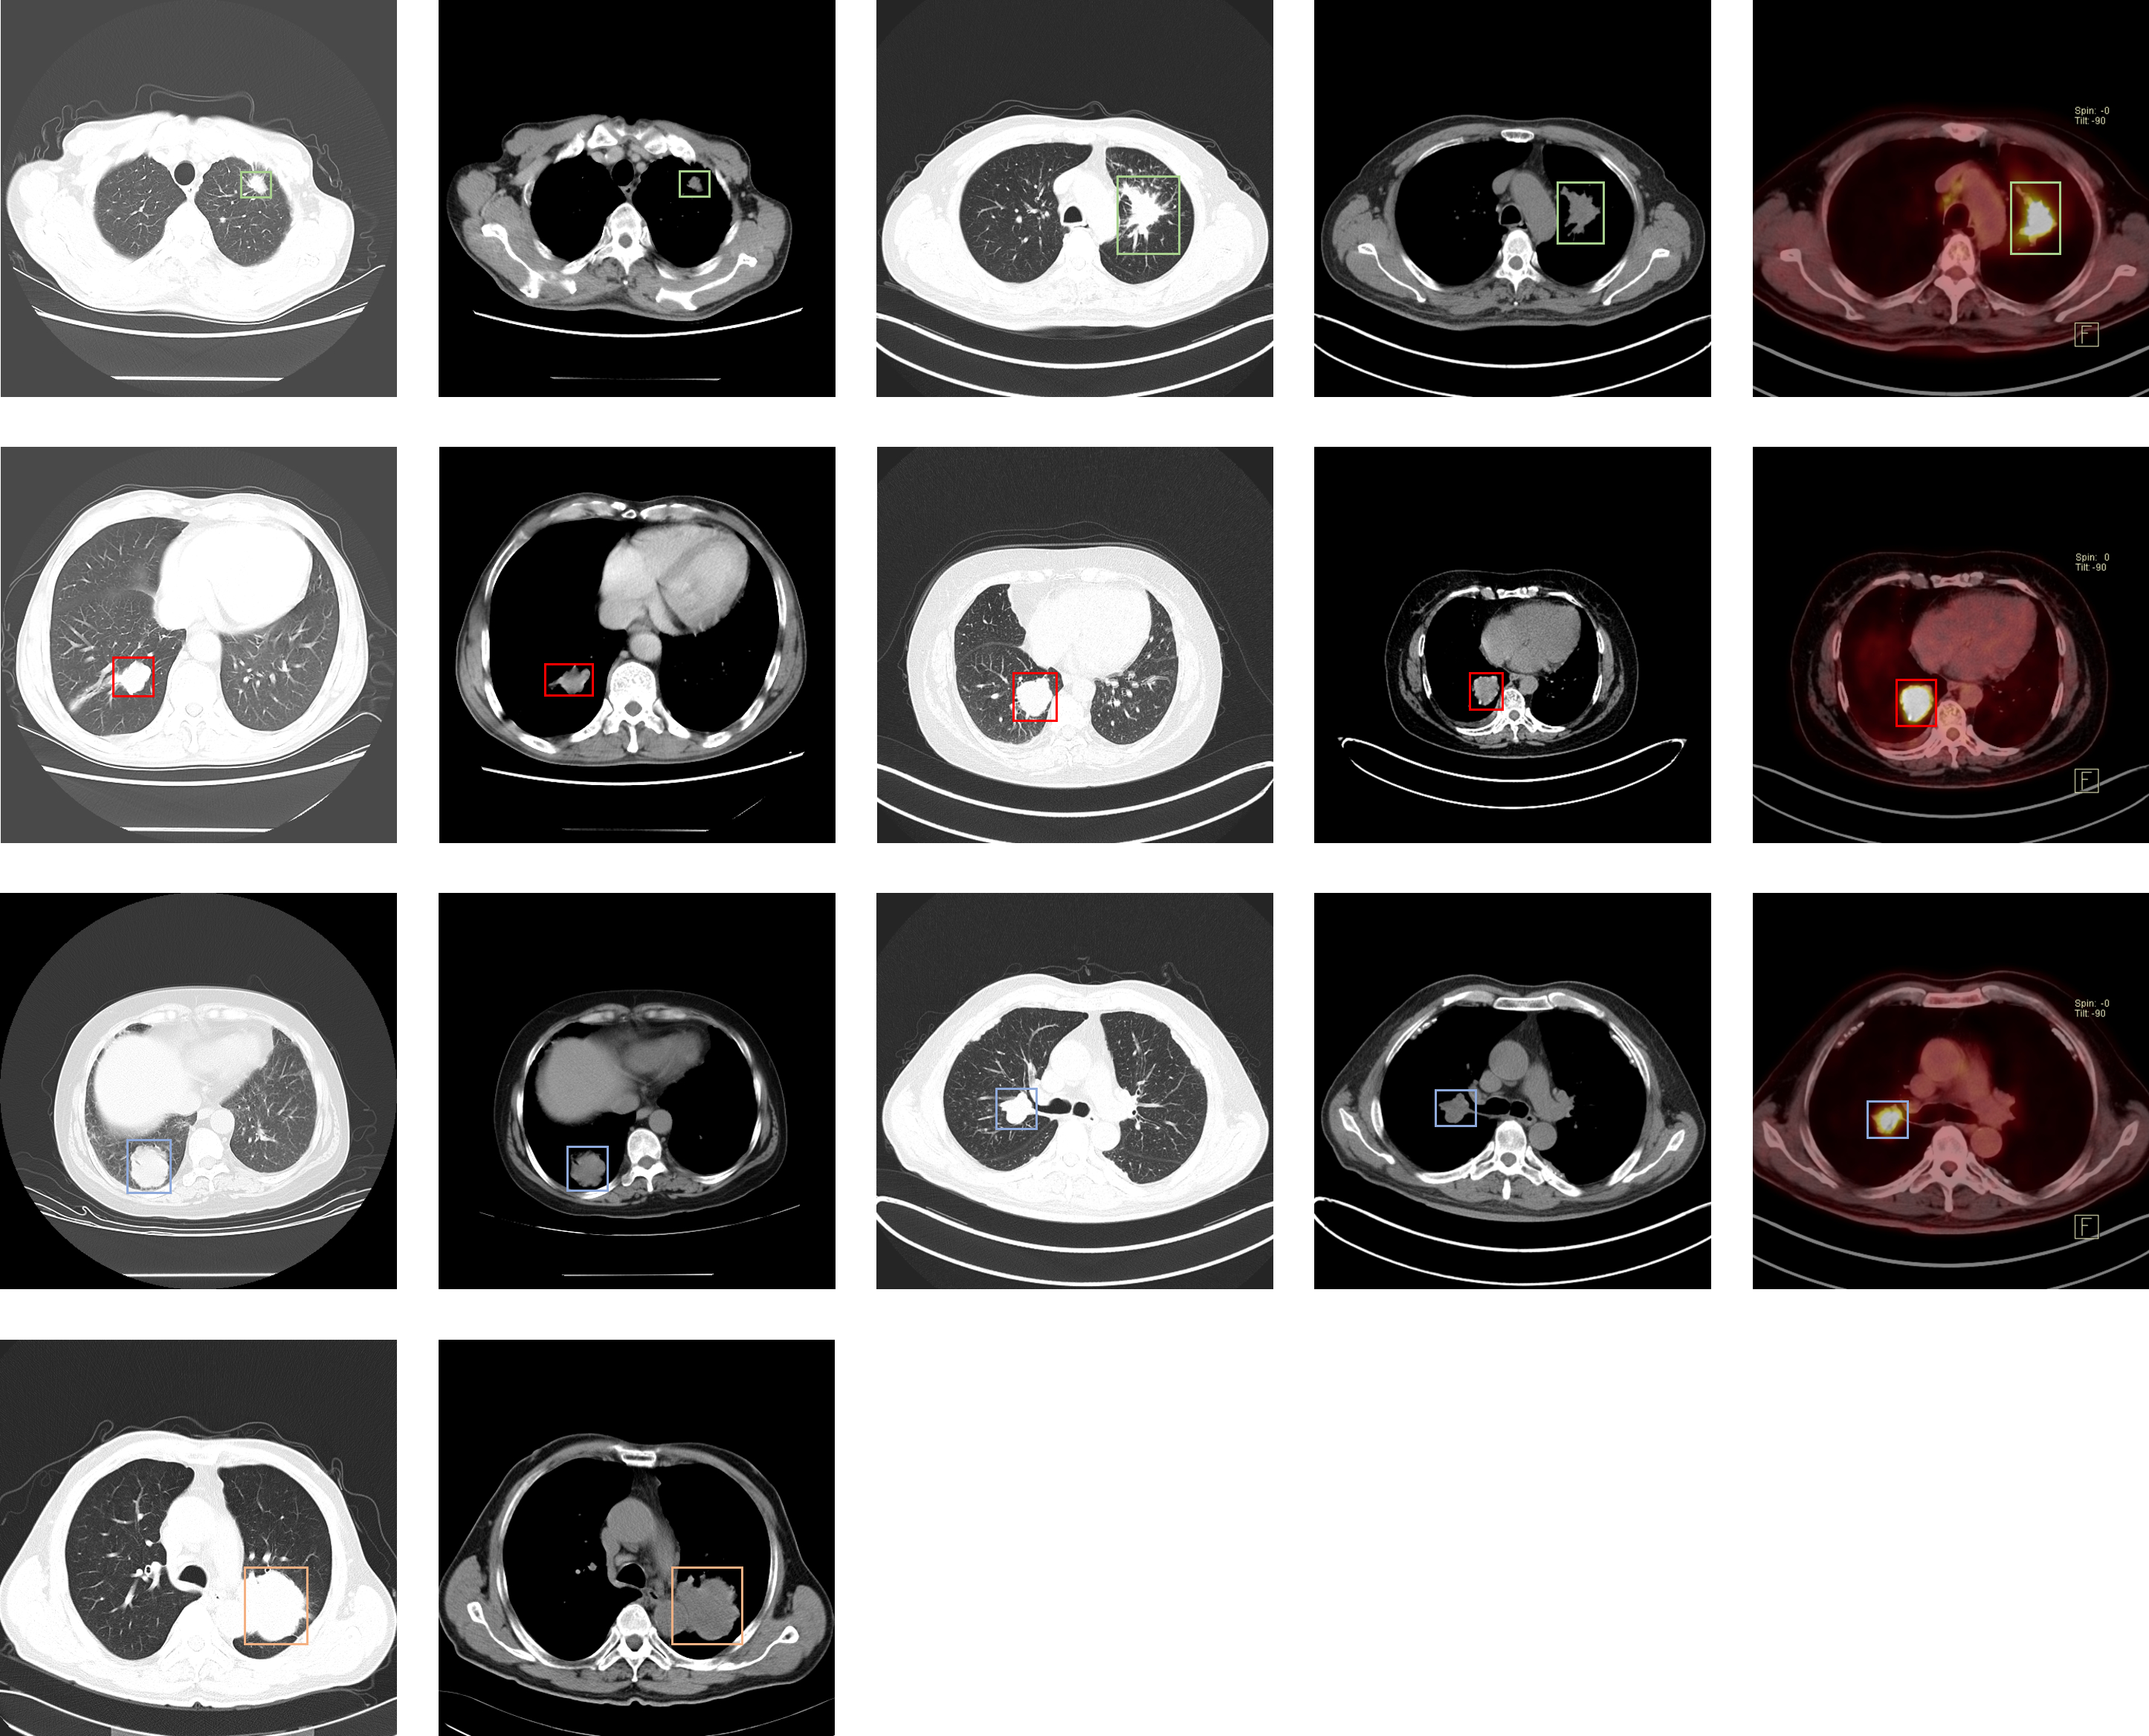

Lung-PET-CT-Dx.png